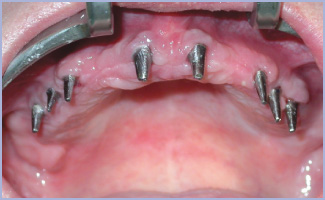

La prima fase chirurgica ha portato all’inserimento di 8 impianti di cui 6 da 3,3 mm di diametro nei settori laterali e 2 da 4,1 mm nei settori anteriori (figg. 4-6).

- Fig. 4

- Fig. 5

- Fig. 6